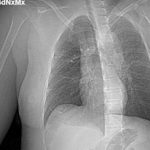

Hình ảnh phim chụp ngực phải của bệnh nhân sưng to do điều trị ung thư vú sai cách.